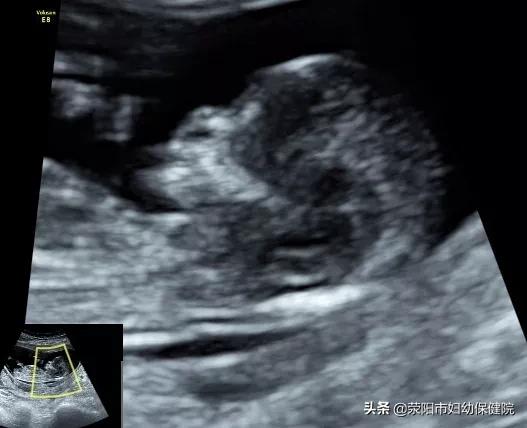

1.NT检查:

NT检查是检查胎儿颈项透明层,排查唐氏综合征的重要检查之一,建议不能省略。一般筛查的时间在11-14周,孕产妇可以根据自己的孕周时间延后,最晚不能超过14周。